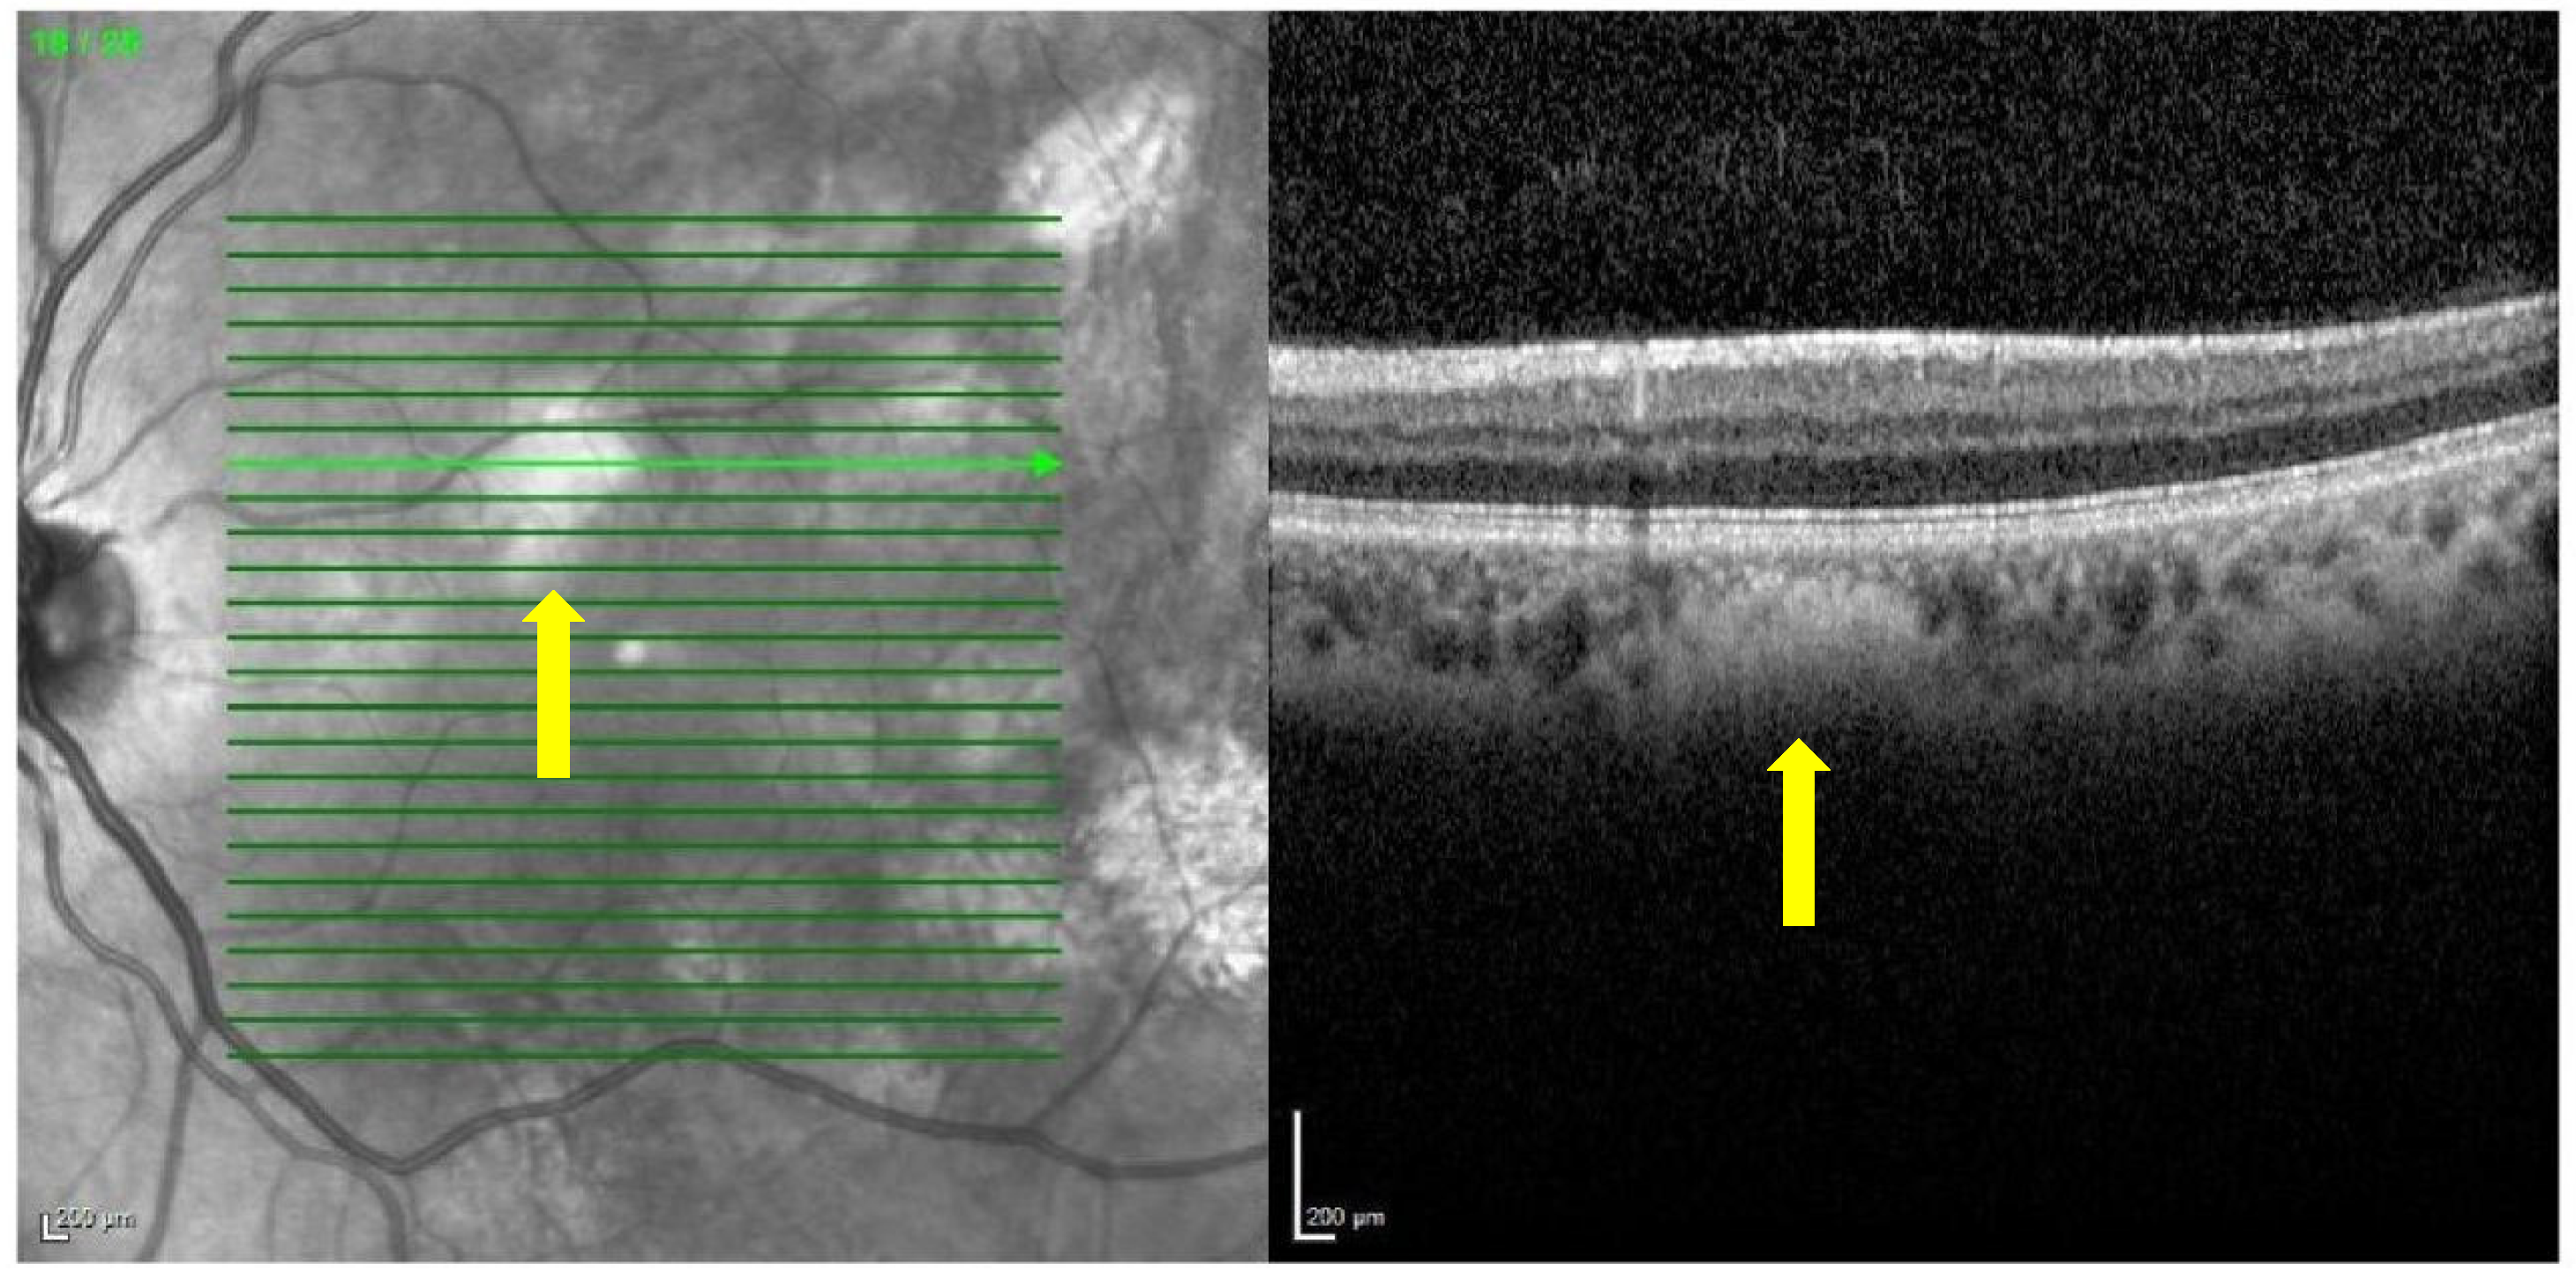

Near-infrared reflectance at 815 nm and red-free (RF) 488 nm images of the posterior pole and mid-periphery of the retina were taken of each patient and monitored with a confocal scanning laser ophthalmoscope (Spectralis HRA+OCT, Heidelberg Engineering, Heidelberg, Germany) (Figure 1) [9]. The combined spectral domain optical coherence tomography (SD-OCT) system allows for simultaneous recording with precise alignment of OCT and topographic images (NIR, RF). Using this technology, which is non-invasive, fast, and abundantly used in routine exams, a good correlation of the topographic image with the morphological changes in the retina and choroid of the macular area was obtained [9]. No dilating eye drops were used before the examination.

Figure 1. Choroidal nodules detected by Spectralis HRA+OCT. The image on the left shows the posterior pole of the retina in the form of a cube, visualized with near-infrared reflectance. The green lines are translated into horizontal slices. The section containing a choroidal nodule (yellow arrow) is selected, and the nodule segmented by OCT is shown in the image on the right.